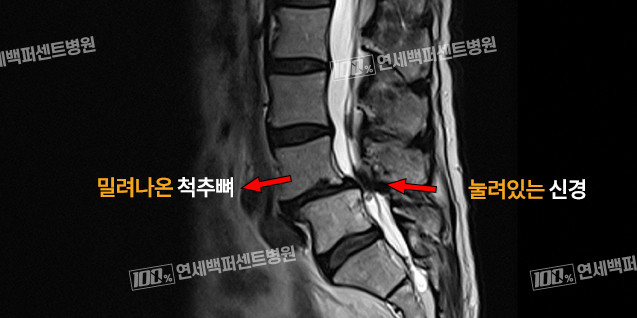

척추뼈의 위아래 마디가 어긋나게 되어 앞이나 뒤로 척추뼈가 미끄러져 나오는 질환입니다.

척추뼈가 밀리면 척추 신경을 보호하고 있던 척추뼈가 오히려 척추신경을 압박하여 통증, 하지방사통과 다리저림 등을 일으킵니다.

척추전방전위증